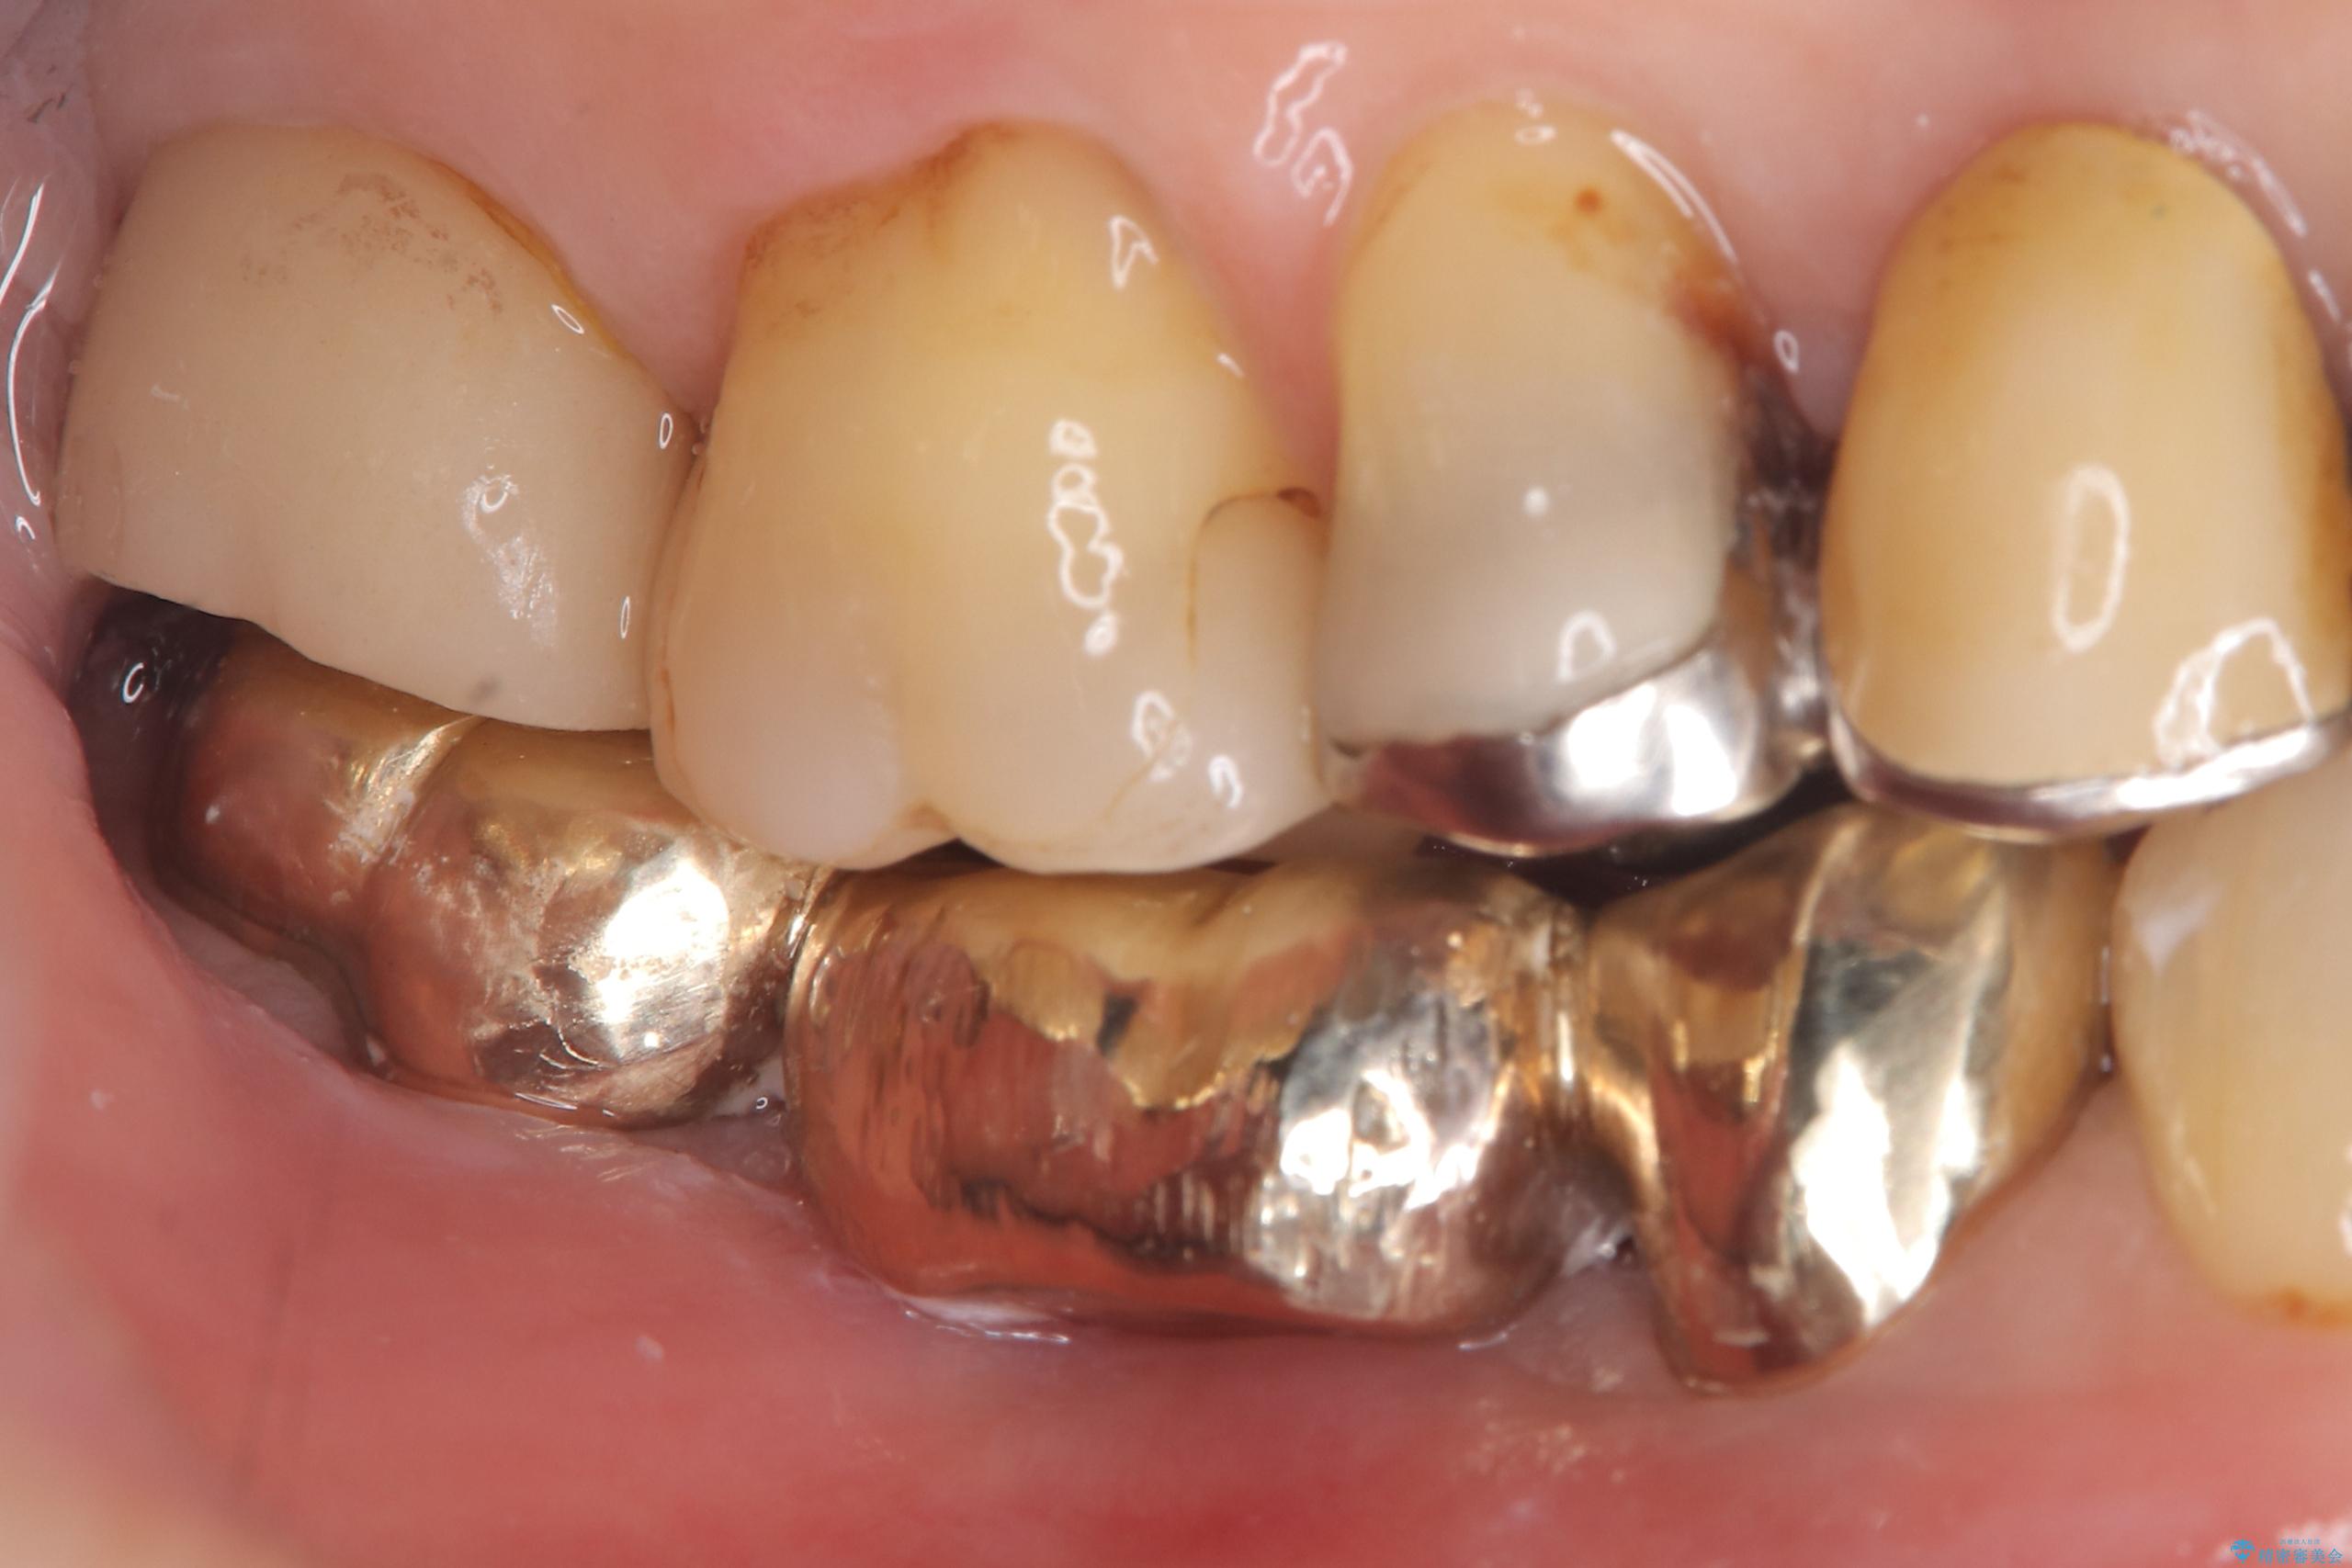

- 主訴:つい先日入れたセラミック(ジルコニア)ブリッジが奥歯部分で割れた。いつも同じ場所で壊れる。これで3度目。

セラミックに比べ、割れづらい金属(ゴールドでのブリッジのやり替えとなりました。

セラミックに比べ、破折リスクの少ない金属を使用したブリッジでのやり替えとなりました。

両支台歯が失活歯のため、どちらかもしくは両方の歯が破折した際、再度ブリッジを除去した治療が必要になるリスクとインプラント治療のご提案もさせていただきましたが、ブリッジでの治療を希望されました。